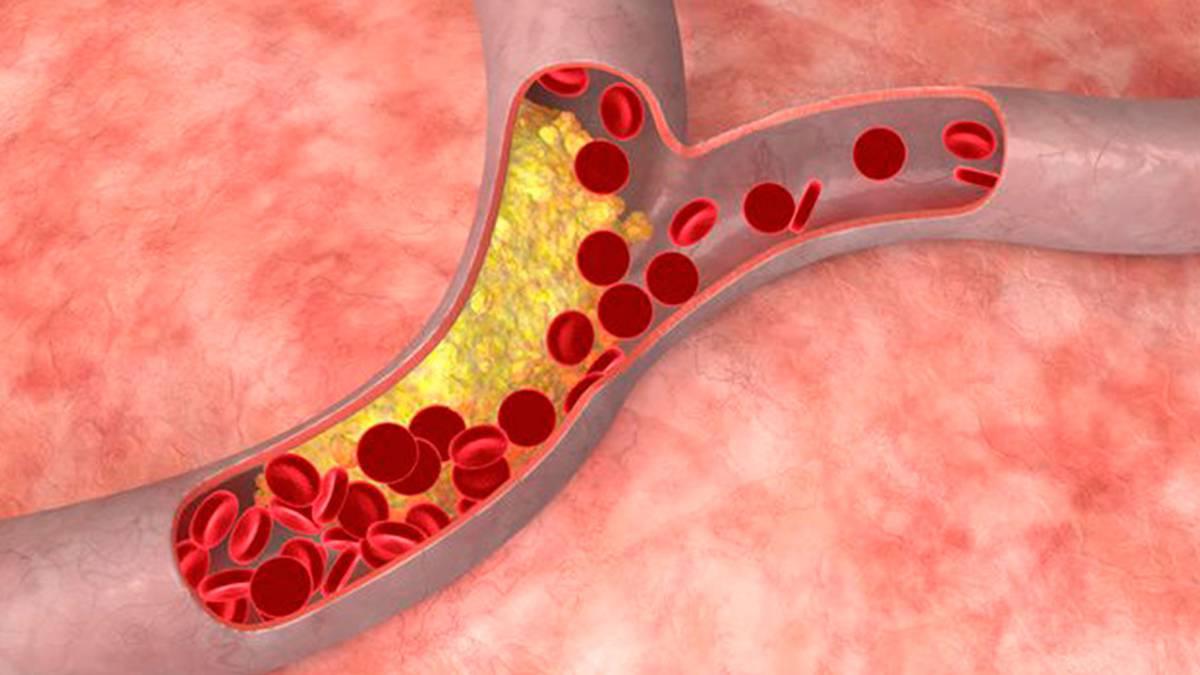

Como ya hemos mencionado, el azúcar sobrante que no pueden consumir las células (que es casi todo), se convierte en grasa. Y aquí entra en juego la hipercolesterolemia. Y es que el consumo de bebidas azucaradas está directamente relacionado con un aumento en los niveles de colesterol “malo” y en una disminución de los del “bueno”.

Se estima que hasta el 55% de la población adulta sufre una forma más o menos grave de hipercolesterolemia, con valores de colesterol LDL (el malo) por encima de los 130 mg/dl de sangre. El principal problema es que el exceso de colesterol no da síntomas, pero este tipo de lipoproteína (lípido + proteína) se va acumulando en las paredes de los vasos sanguíneos, cosa que puede derivar en un infarto de miocardio o en un ictus.

Como podemos deducir, el consumo de bebidas azucaradas, por su relación tanto con la obesidad como con la hipercolesterolemia, está detrás de muchas enfermedades cardiovasculares. Estas patologías del corazón y de los vasos sanguíneos son la principal causa de muerte en el mundo.

En este sentido, excesos con los refrescos aumentan el riesgo de sufrir infartos de miocardio, cardiopatías, accidentes cerebrovasculares, embolias pulmonares, arritmias, etc. El sistema circulatorio nos mantiene vivos. Por ello, cuando sufre daños, todo el organismo nota las consecuencias.

Debido al taponamiento de vasos sanguíneos inducido por la hipercolesterolemia, el consumo de bebidas azucaradas también se vincula con la hipertensión arterial. Es decir, la fuerza que ejerce la sangre contra las paredes de los vasos sanguíneos es demasiado alta. Y aunque entran en juego factores genéticos, los malos hábitos alimenticios son pieza fundamental.